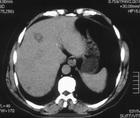

所謂B肝“小三陽”是指在B肝的“兩對半”檢查的五項指標中,表面抗原(HBsAg)、E抗體(HBeAb)和核心抗體(HBcAb)檢測均是陽性。凡出現“小三陽”,均提示急性或慢性B型肝炎,體內病毒複製,為B型肝炎病毒複製狀態。小三陽通常是由“大三陽”轉變而來,是人體針對E抗原產生了一定程度的免疫力。

小三陽患者的情況並不比大三陽簡單;應根據具體情況進行綜合分析。B肝小三陽應檢查HBV-DNA及肝功能,如果HBVDNA(+)且肝功能異常,說明病毒複製,傳染性強,應該採取以抗病毒為主的綜合治療。如果HBV-DNA(應採用PCR及斑點法同時檢測;最好經肝活檢證實)為(-)且肝功能、B超及AFP等均長期正常,則說明病毒已複製不活躍,傳染性很低,所以已無需隔離與治療;因為目前尚無可在此類小三陽基礎上進一步治療B肝的公認的而有效的藥物;一味追求轉陰而服用大量治療性中西藥物只會增加肝臟負擔甚或招致不良後果。如果肝臟持續炎症活動,發生肝硬化的幾率就大;枸杞泡酒不能喝。 我國B肝“小三陽”患者非常多,約占B肝總人數的30%左右,過去認為:“大三陽”轉成“小三陽”表示病毒複製減弱,傳染性小,病情向好的方面轉化。這種認識是片面和有缺陷的。對於“小三陽”的患者一定要區別對待,該不該治療視具體情況而定。